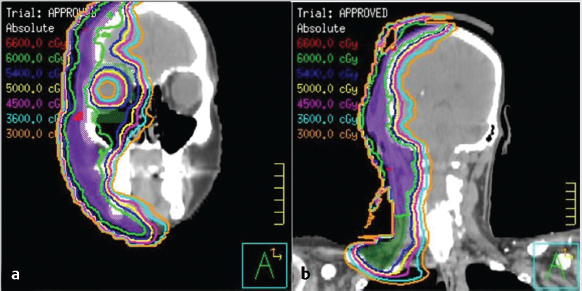

7 Role of Radiotherapy in the Treatment of Skin Malignancies Non-melanomatous skin cancers (NMSC), specifically basal cell carcinoma (BCC) and squamous cell carcinoma (SCC), are the most common malignancies in the United States. They are primarily managed surgically and carry an excellent prognosis, with a 1 to 5% rate of disease recurrence after complete excision and only exceedingly rare instances of distant metastasis. Historically, radiotherapy played a prominent role in the definitive management of these cancers as an alternative to surgical resection, especially in cosmetically sensitive areas. With the improvement in surgical techniques in recent decades, especially the widespread use of Mohs micrographic surgery (MMS), the use of curative radiation for skin cancers has declined. However, radiation is still commonly used in the definitive setting for patients with NMSC who are poor surgical candidates or have larger lesions in cosmetically sensitive regions of the face, and in the postoperative setting for more advanced tumors that have high-risk pathologic features that are associated with excessive risks of locoregional recurrence after surgery alone. Radiotherapy plays a similar role in the postoperative management of cutaneous melanoma. Radiation also offers excellent palliation for noncurable patients. This chapter reviews common indications, dose and fractionation schedules, techniques, and oncologic and cosmetic outcomes for radiotherapy for NMSC and melanoma ( Both surgery and RT can offer excellent cure rates for the management of early-stage NMSC. Surgery is typically the preferred method of treatment, given it can be performed in a single session, and has been associated with superior oncologic and cosmetic outcomes. One prospective randomized study compared the outcomes of MMS and definitive RT in 347 patients with less than 4 cm BCC of the face. The local failure rate was 0.7% for patients treated with MMS and 7.5% for patients treated with RT. Additionally, the cosmetic outcome was rated “good” or better more often in those patients who underwent surgery (87 vs. 69%).1 Though the technique of RT was not controlled (55% received interstitial brachytherapy and 45% received orthovoltage therapy), which could have affected the quality of the comparison, as the only randomized study, this trial remains pivotal in guiding medical decision making. A variety of factors can influence the decision to favor RT rather than surgery for NMSC. Typical contraindications to definitive RT include very large tumors and those with bone and/or cartilage invasion, given that control rates are typically inferior, as well as recurrent tumors that have been previously radiated or arise in an area of previous radiotherapy. Radiation should also be avoided in patients with genetic radiosensitivity syndromes, such as xeroderma pigmentosum and basal cell nevus syndrome, and in those with active connective tissue diseases, such as scleroderma and systemic lupus erythematosus.2 Patients who are candidates for definitive RT include those with unresectable disease, older patients with comorbidities limiting their surgical options, and patients with lesions involving the eyelid, canthi of the eye (especially those who carry surgical risk to the lacrimal duct), external ear ( Fig. 7.1 A modern linear accelerator, capable of delivering photon and electron radiotherapy with image guidance provided by cone beam CT (red arrow). A robust literature, much of it older when RT was more commonly used, supports the safety and efficacy of definitive RT for many of these aforementioned types of patients. A review of 986 BCC and SCC of the skin overlying the eyelid treated with definitive RT demonstrated a 5-year cure rate of 96.4%.3 A review of 334 BCC and SCC of the external ear at the Princess Margaret Hospital treated with definitive RT demonstrated a 2-year local control rate of 87%, with severe late toxicity noted in only 7% of patients.4 A review of 100 patients with SCC of the nasal skin at the Princess Margaret Hospital treated with definitive RT demonstrated a 2-year local control rate of 90%, with no severe toxicities observed.5 Fig. 7.2 (a) SCC of the helix of the left ear with bleeding (baseline). (b) After treatment with definitive radiation therapy (50 Gy in 20 fractions with electrons). There was complete remission with excellent cosmesis. Fig. 7.3 (a) A 96-year-old patient with right retroauricular BCC, T2N0M0 (baseline). (b) One month after treatment with definitive radiation therapy (50 Gy in 20 fractions with electrons). While definitive RT monotherapy can provide effective tumor control for T1–3N0 NMSC, T4 tumors and those with nodal metastases demonstrate inferior outcomes. Initial surgical management is recommended in these patients, often followed by adjuvant radiotherapy. T4 disease is defined as tumor invasion into the axial or appendicular skeleton or perineural invasion (PNI) of the skull base. The University of Florida reported a local control rate of just 53% at 5 years in patients with T4 BCC and SCC.6,7 In a review of 68 T4 BCC and SCC of the skin of the head and neck treated with definitive RT, local control rates were lower in patients with recurrent disease, compared to primary lesions (41 vs. 67%; p = 0.07) and the three most important prognostic indicators for inferior local control and cause-specific survival rates were bone involvement (p < 0.01), recurrent lesions (p < 0.01), and nerve involvement (p < 0.02).6 Even the more favorable lesions had local control rates of less than 70%. Similarly, a large retrospective review which included 531 BCC and SCC treated with definitive RT demonstrated local control rates of 94 and 89% for primary BCC and SCC tumors, respectively, and 86 and 68% for BCC and SCC recurrent tumors, respectively.8 In patients with nodal metastases, locoregional recurrence rates with definitive RT alone range from 30 to 50% and cancer-related mortality is as high as 30%.9 Such suboptimal outcomes support the use of intensification of treatment and multimodal therapy for these patients with advanced disease. In patients who are not eligible for initial surgical resection, concurrent cisplatin-based chemotherapy can be considered to enhance the effectiveness of radiotherapy. While there is no high-quality evidence demonstrating clear benefit to such an approach in cutaneous malignancies, many head and neck oncologists extrapolate from the mucosal SCC of the head and neck, where concurrent chemotherapy significantly improves disease control and survival in the setting of locally advanced disease treated nonoperatively.10 Fig. 7.5 A patient with multifocal BCC 3 months after treatment with definitive radiation therapy (40 Gy in 10 fractions with electrons). Postoperative RT is rarely used for BCC. Patients with BCC have an exceedingly low risk of recurrence after surgery alone, and even patients with a positive margin, focal cartilage invasion, or PNI are often still candidates for close observation and salvage re-resection if needed.11,12 However, postoperative RT is often considered in cases where there are persistently positive margins after multiple resections, T4 disease that extensively invades bone or soft tissue, lymph node metastasis, or clinically apparent PNI ( Postoperative RT is much more commonly used in resected SCC ( Retrospective data have demonstrated high rates of local recurrence in patients with T4 tumors managed with surgery alone.7 In addition, the rate of occult lymph node metastasis is high, ranging from 29 to 50%, in patients with advanced T-stage disease. In patients with deeply infiltrative (≥ 8 mm) tumors, or tumors that extensively invade deep subcutaneous fat, occult lymph node metastasis can be as high as 30%.9 Patients with recurrent primary tumors, PNI, lymphovascular space invasion, and those that are immunosuppressed are at significantly higher risk for having lymph node metastases and should undergo careful evaluation for regional disease with a contrast-enhanced diagnostic neck computed tomography (CT) and/or a positron emission tomography scan.14,15,16 In these patients, sentinel lymph node biopsy and/or neck dissection is recommended in conjunction with resection of the primary tumor. Postoperative RT can also be useful as an elective treatment to the undissected neck. Fig. 7.6 (a) A patient with right brow/forehead SCC (baseline). (b) One month after definitive radiation therapy (45 Gy in 15 fractions with electrons). Fig. 7.7 (a) An 88-year-old man with left temporal SCC in situ (baseline). (b) One month after treatment with definitive radiation therapy (30 Gy in five fractions with electrons). For patients with clinically involved lymph nodes, a therapeutic neck dissection followed by postoperative RT is the current standard of care. Although lymph node metastases are rare in SCC of the skin overall (~ 5%), they are clearly associated with a poor prognosis. After neck dissection alone, locoregional recurrence rates are 11 to 38% and even after multimodality therapy, the 5-year disease-free survival rates are 60 to 70%. Independent predictors of worse survival in this population include increased nodal size ≥ 3 cm, multiple lymph node involvement, extracapsular extension, incompletely excised nodes, and surgery monotherapy.15,16,17 A review of 167 patients in Australia with SCC metastatic to the parotid or cervical nodes compared outcomes for surgery versus combination of surgery and postoperative RT at a median dose of 60 Gy in 30 fractions. The use of postoperative RT was associated with significantly lower rates of locoregional recurrence (20 vs. 43%), and higher 5-year disease free (73 vs. 54%; p = 0.004), and 5-year overall survival (66 vs. 27%; p = 0.003) compared to patients who received surgery alone.16 Similar results supporting the benefit of postoperative RT for locoregional control and 5-year disease-free survival in patients with cutaneous SCC metastatic to lymph nodes and/or periparotid lymph nodes have been reproduced in a number of retrospective reviews.18,19,20,21 For patients who received lymph node dissection for primary SCC located on the trunk or extremities, postoperative RT is typically recommended when multiple nodes are involved or extracapsular extension is present. Similar to mucosal SCC of the head and neck, RT can be avoided in immunocompetent patients with a single involved lymph node, smaller than 3 cm, without extracapsular extension on parotidectomy or cervical lymph node dissection, as rate of regional recurrence is less than 5%.22 Fig. 7.9 A 91-year-old man with a history of extreme kyphosis and multiple facial SCC, who presented with a rapidly enlarging right neck mass, treated with surgical resection and free flap reconstruction. (a) Axial slice depicting isodose coverage of the neck bed with electron radiation therapy. (b) Extreme kyphosis dose coverage using 30 Gy in five fractions twice weekly. Fig. 7.10 A 63-year-old man with multiple recurrent SCC of the right temple with Mohs map overlying the site of the tumor. Fig. 7.11 (a) Coronal CT slice of dose distribution for postoperative radiation therapy after Mohs surgery for tumor depicted in PNI, while not common (5–10% of SCC), is another important risk factor for recurrence that should be weighed in the decision to administer adjuvant RT. PNI is typically divided into clinical and microscopic PNI. Clinical PNI is defined by neurologic manifestations, most commonly involving the trigeminal or facial nerves, leading to pain, paresthesias, paralysis, formication (the sensation of bugs crawling on the skin), or radiographic evidence of nerve enhancement.23,24 Microscopic PNI is appreciated only histologically and is identified after surgery in a patient who was asymptomatic preoperatively. PNI is important given it is associated with increased risks of local recurrence as well as regional and distant metastases. Factors associated with increased risk for SCC with PNI include male sex, tumor size greater than 2 cm, midfacial tumor location, recurrent tumor, and poorly differentiated subtypes.25 The degree of PNI is predictive of risk of recurrence; therefore, a careful history as well as physical and imaging examination is critical. Magnetic resonance imaging (MRI) has the advantage of identifying the extent of macroscopic disease through nerve enlargement or enhancement or obliteration of the normal fat plane surrounding a nerve ( The difference between clinical and microscopic PNI was highlighted in a series from the University of Florida which compared the outcomes of patients with PNI treated aggressively with surgery and postoperative RT. Those with clinical PNI had significantly lower 5-year rates of local control (57 vs. 90%; p = < 0.001) and overall survival (57 vs. 69%; p = 0.03) compared to those found to have microscopic PNI.13,23 RT is therefore always recommended in cases of clinical PNI. The role of postoperative RT in patients with pathologic PNI is less clear. Lin et al found that focal versus extensive microscopic PNI carries different prognoses, with relapse-free survival better in the former group (86 vs. 74%; p =0.1).24 Unfortunately, the distinction between focal and extensive was not well defined. As such, adjuvant RT is not recommended in immunocompetent patients with nonrecurrent disease, in whom one or two isolated areas of PNI are found in small unnamed nerves, with a diameter of less than 0.1 mm, given the outcome is expected to be fairly good with surgery alone. However, patients with microscopic PNI, that is multifocal, involves larger nerves (> 0.1 mm in diameter) and named nerves, or occurs in immunosuppressed patients, are at higher risk and thus adjuvant RT is recommended.2,25 For irradiation of clinical PNI, the clinical target volume should include areas at high risk of failure, specifically the involved nerve, the portion of the nerve proximally at the skull base, the distal skin innervated by the nerve, major communicating branches, and the compartment in which the nerve is embedded.26 For example, for patients with CN VII involvement, the area of treatment should be tracked back to the nerve’s exit through the stylomastoid foramen, with care taken to administer adequate coverage of the geniculate ganglion by avoiding excessive restriction of the radiation dose delivered to the ipsilateral cochlea. Similarly, with V1/V2 nerve involvement, the gasserian ganglion in Meckel cave and the cavernous sinus should be targeted ( Another consideration highly relevant to radiation field design is the observation that PNI may also be associated with increased nodal failure in addition to recurrence in the tumor bed and along the nerve pathway. Lin et al demonstrated that patients who developed recurrent disease with pathologic PNI had a significantly higher risk of local recurrence (40 vs. 19%; p < 0.01) as well as regional recurrence (29 vs. 5%; p = 0.02).24 It is important to consider the location of the lesion in such scenarios, given that tumors on the scalp, for example, may be less likely to metastasize to lymph nodes, compared to cheek, ear, or nasal skin lesions. Understanding the drainage patterns of these tumors is crucial (e.g., parotid nodes for head and neck sites, axilla for trunk and extremity lesions) and should be incorporated into radiation targeting. Fig. 7.13 (a) Axial radiation planning CT slice depicting inferior alveolar nerve (solid red) covered by isodose lines. (b) Axial radiation planning CT slice depicting left cavernous sinus and temporal musculature (solid light blue) covered by isodose lines. (c) Axial radiation planning CT slice depicting course of V2 into cavernous sinus (solid red) covered by isodose lines. (d) Sagittal radiation planning CT slice depicting coverage of V1 and V2 back to the cavernous sinus (solid red) covered by isodose lines. Fig. 7.14 (a) A 67-year-old man with history of recurrent right auricular SCC treated with multiple surgical resections and prior irradiation who presented with recurrent disease at the right skull base (red arrow). (b) Sagittal radiation planning CT slice depicting recurrent disease covered by 70 Gy isodose line (black line). Melanoma is believed to be a relatively radioresistant malignancy. Therefore, maximal surgical resection is paramount in the management of these tumors. RT has limited benefit in achieving long-term control in the presence of gross disease. RT is delivered to gross melanoma in patients deemed to have unresectable disease, or those with rapid postoperative recurrence who have failed surgical management. In these cases, higher doses per fraction are generally preferable and the intent of treatment is largely palliative. Adjuvant radiotherapy to the primary tumor bed, nodal basin, or both, has been studied as a means of reducing locoregional recurrence. If adequate margins are obtained, local recurrence for primary melanoma is infrequent, with rates consistently reported to be less than 5%.27,28 However, there is a smaller subset of patients with higher rates of failure in the tumor bed, including deeply invasive T4 disease, the presence of satellitosis, the presence of desmoplastic subtype, or persistently positive margins despite multiple attempts at excision. In these cases, adjuvant RT to the primary tumor bed should be considered ( O’Brien and colleagues analyzed 629 patients with head and neck melanoma and found that increased local recurrence rates were associated with increased tumor thickness: < 0.76 mm, 2%; 0.76 to 1.49 mm, 5%; 1.5 to 3.99 mm, 15%; and ≥ 4 mm, 20%.29 Typically, adjuvant RT is considered for T4 tumors, although typically reserved for those with additional high-risk features. One of which is satellitosis, which represents discontiguous sites of disease within 2 cm of the primary tumor and is known to be a marker of increased recurrence risk.30 Desmoplastic melanoma is a rare histologic subtype (1% of all melanomas) and is characterized by spindle-shaped cells with associated collagen production. This subtype is often associated with perineural spread and local recurrence rates have been reported as high as 20 to 50%.31,32 In these cases, based on the relatively higher risk for local recurrence, adjuvant RT should be considered. More extensive literature guides the use of adjuvant RT to nodal basins, both in the elective setting and following lymph node dissection.33,34 Data supporting the benefit of RT in reducing regional recurrence come from the randomized phase III study by Burmeister et al in which higher risk patients were randomized to surgery and lymph node dissection with or without adjuvant radiation to the nodal basin.35 Eligible patients had one of the following features associated with increased failure rates: 1. Serum lactate dehydrogenase < 1.5 times the upper limit of normal and the presence of extracapsular extension (ECE). 2. ≥ 1 involved parotid node of any size. 3. ≥ 2 involved cervical nodes and/or ≥ 3 cm of tumor within a node. 4. ≥ 2 involved axillary nodes and/or ≥ 4 cm of tumor within a node. 5. ≥ 3 involved inguinal nodes and/or ≥ 4 cm of tumor within a node, and/or recurrent disease.27,30 Importantly, no systemic therapy was delivered in this trial. In the 217 patients included on the study, those who received RT were significantly less likely to experience regional recurrence compared to those in the observation arm (18 vs. 33%; p = 0.041). As distant metastasis is the predominant mode of melanoma disease failure, it was not surprising that an improved rate of regional control did not translate into an overall survival average (54 vs. 44%; p = 0.12). The most common Grade 3 or 4 adverse events were seroma and wound infections, which were equivalent in both arms.35 The lack of systemic therapy in this study as well as the lack of a survival difference with the use of RT has raised the question of the true benefit of adjuvant RT for all patients eligible for this study. That said, it reinforces the guiding principle where locoregional control is a priority, and in a case with extensive nodal disease, especially with extranodal extension and significant soft-tissue involvement, adjuvant RT should be considered as a proven way to reduce rates of locoregional recurrence ( Fig. 7.15 A 72-year-old man with pT3N2cMx melanoma of the scalp with ulceration and satellitosis treated with wide local excision, free flap reconstruction, ipsilateral neck dissection, and adjuvant RT to the primary tumor bed. (a) Postoperative image. (b) Axial radiation planning CT slice demonstrating bolus material (red arrow) for achieving adequate surface dose.

Fig. 7.12). CT offers the advantage of detecting whether bone erosion is present, particularly tumor invasion into foramina associated with cranial nerves.

Fig. 7.13). Targeting the nerve root as it exits the brainstem should be considered for nerves that are radiographically involved at the skull base. For patients with unresectable disease invading the skull base, high-dose radiation (70 Gy), with or without concurrent chemotherapy, is required (